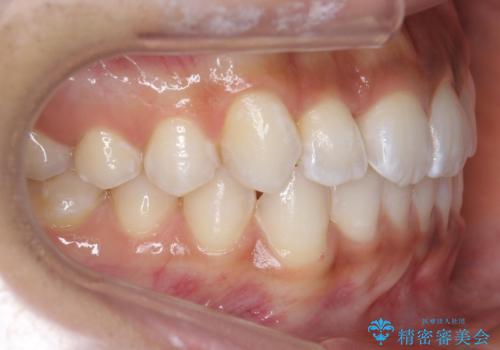

前歯のがたつき 1年かからず治療 マウスピース矯正

- 前歯のがたつきを主訴に来院。

インビザラインで歯を抜かずに並べました。

マウスピースの延長(リファインメント)もなく、短期間で綺麗に並びました。